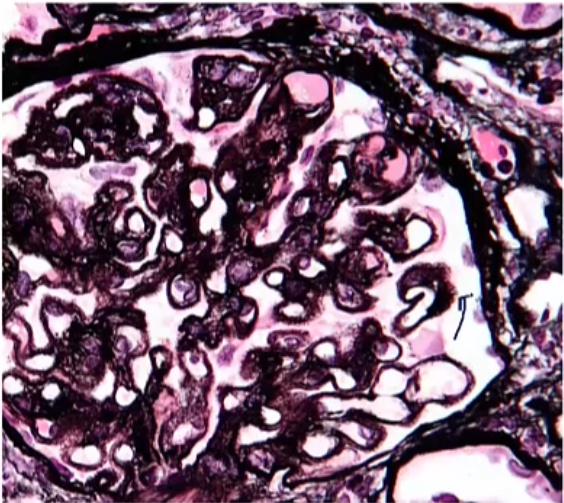

thick knots in string: Associated with membranous glomerulonephritis

3 string: Associated with membranoproliferative glomerulonephritis. Tram track appearance

if hypercellular: membranoproliferative

Membranous Nephropathy